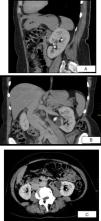

Laboratory tests showed normal blood cell counts, coagulation parameters, electrolytes, and renal and hepatic tests. No rhabdomyolysis nor hemolysis were present. Urine dipstick revealed a specific gravity of 1.010, 3+ hemoglobin and no protein; the microscopic exam showed 168 red blood cells per high power field, but no casts or white blood cells. Urine cultures, including for mycobacteria, were negative. She had no anomalous cells in cytology and a normal cystoscopy. A computed tomography scan (Fig. 1A–C) suggested renal papillary necrosis and excluded other abnormalities. There were no criteria for diabetes mellitus. Hemoglobin's electrophoresis showed the presence of an abnormal hemoglobin (Fig. 2) which was subsequently documented to be HbS. A molecular study revealed an heterozygosity for the hemoglobin sickle mutation of the β-globin gene (HBB:c.20A>T) establishing a diagnosis of SCT.

A, B, C: Sagital, coronal and axial sections of abdominal computed tomography revealing structural heterogeneity of the left renal parenquima with diminished enhancement at the tip of the medullary pyramid and the presence of small cavities filled by contrast on the borders of the small calices – aspects highly suggestive of papillary necrosis ischemia.